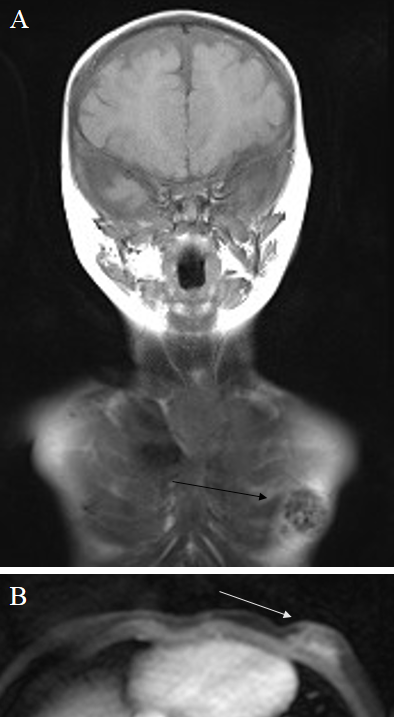

The hypertrophic boy was delivered by an unaffected mother 7 weeks prior to the predicted delivery date. Medical records disclosed macrocephaly at birth, in addition to dysregulated muscle tone, neonatal infection and respiratory distress syndrome, and hyperbilirubinaemia. During the next few months, retardation of motor skill development became obvious and CAL-spots of the skin were recorded. Ultrasonographic follow-up investigations of hydrocephalus revealed stable volumetrics of the brain tissues. The ultrasound images of gynaecomastia were repeatedly judged as inflammatory in origin. Prior to surgical therapy, whole-body magnetic resonance imaging (MRI) was performed. MRI showed regular intracranial structures according to age and, in particular, ventricles of normal size and no optic nerve glioma. On the left thoracic side, submammary tissues were identified that were confined to the pectoral soft tissue, weakly hyperintense on T2-weighted images without the typical signal constellation indicating a neurofibroma (Figure 2 [Fig. 2]). Differential diagnosis based on MRI was plexiform neurofibroma or gynaecomastia.

Figure 2: Magnetic resonance images of the NF1-affected child A) On T1-weighted images (coronal plane), an inhomogeneous roundish space-occupying lesion is visible in the left breast region. B) The same region is hyperintense on T2-weighted images (axial plane, cropped image).